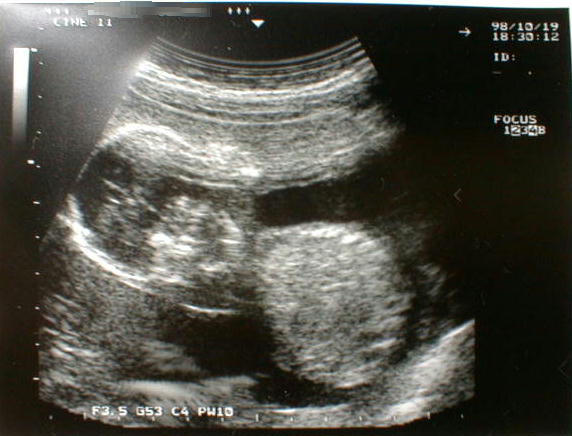

第18週に入った胎児の写真です。

(大きさは、分かりません・・・)

順調に育っているとの事でした。

性別は、赤ちゃんのからだの向きにより不明でした。